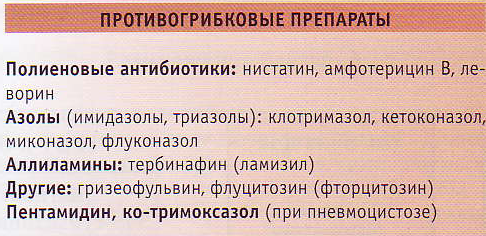

Механизмы действия антимикотиков: схемы и изображения